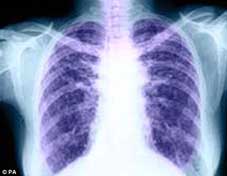

Lần đầu tiên, một lá phổi hiến tặng bị tổn thương đã được chỉnh sửa và ghép cho bệnh nhân. Bình thường phổi hiến tặng nếu không đạt tiêu chuẩn sẽ bị bỏ đi. Tuy nhiên, áp dụng kỹ thuật mới kết hợp thuốc với tế bào gốc, các bác sĩ Canada đã biến lá phổi suýt bị vứt bỏ thành lá phổi đủ tiêu chuẩn ghép cho bệnh nhân.

Phổi hiến tặng thường được lấy từ người tử vong do chấn thương sọ não để ghép cho bệnh nhân. Tuy nhiên, do khi ngừng hoạt động não bộ thường giải phóng các men (enzyme) gây viêm nhiễm nên chỉ khoảng 15% phổi đáp ứng tiêu chuẩn trong phẫu thuật ghép tạng. Những phổi tốt sẽ được trữ lạnh và có thể dùng để ghép trong vòng 6 đến 8 giờ.

Với qui trình mới, phổi hiến tặng sau khi được tách khỏi tử thi sẽ được chuyển đến ngăn bảo vệ nối với hệ thống thông gió và bộ phận lọc để được truyền dung dịch mang ôxy. Nhiệt độ của phổi được tăng lên trong 30 phút cho đến khi đạt đến 37oC – ở ngưỡng nhiệt độ này, phổi có thể được bảo quản từ 12-18 giờ, cho phép các bác sĩ đánh giá chất lượng của tạng để có hướng xử lý thích hợp. Trong thời gian này, phổi cũng sử dụng một phần khả năng tái tạo tự có để phục hồi tương tự như khi ở trong cơ thể.

Các nhà khoa học Canada cho rằng kỹ thuật của họ có thể áp dụng cho mọi nội tạng, và mở ra triển vọng thành lập ngân hàng nội tạng tương tự như ngân hàng máu, nơi xét nghiệm và lưu trữ nội tạng hiến tặng. Kỹ thuật “tút” nội tạng này đã được thử hiện thành công trên 4 bệnh nhân ghép phổi.